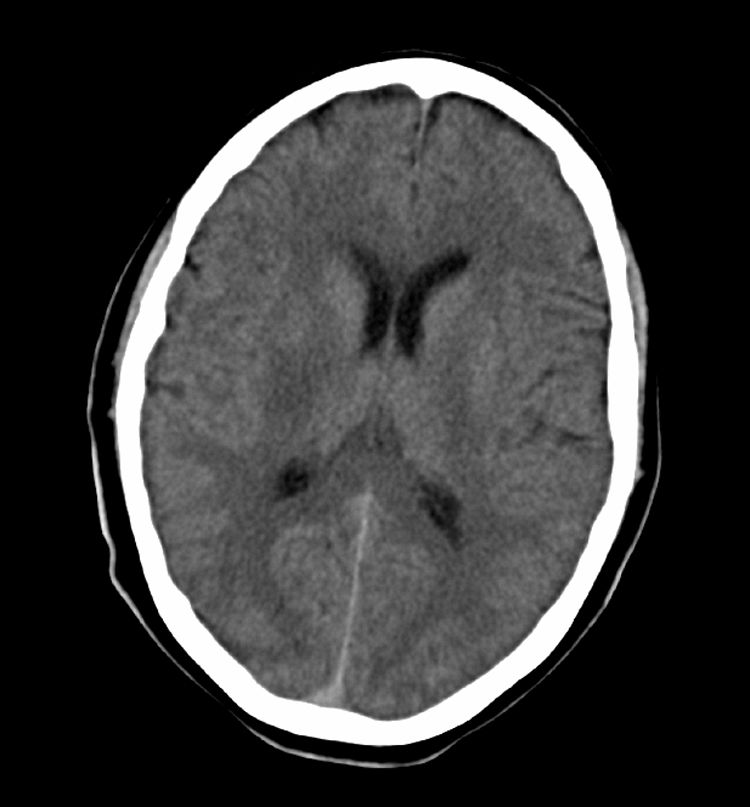

We present the case of a man aged 52 with a history of smoking, alcohol abuse, and obstructive sleep apnoea syndrome (OSAS), who was undergoing treatment with CPAP. He experienced 2 sudden-onset transient episodes of left-sided weakness and difficulty articulating words, each lasting less than 30minutes. He was treated in his referral hospital, where he suffered a third identical episode before being sent to our hospital. On the way, he suffered another episode in the ambulance. Upon arrival at the hospital, he presented mild right faciobrachiocrural hemiparesis and mild dysarthria (4 on the NIHSS scale). Computed tomography (CT) and intracranial CT angiography yielded normal results. The patient was transferred to the stroke unit for monitoring. After 40minutes, the patient's clinical condition worsened; he presented left hemiplegia, an NIHSS score of 9, and low blood pressure (minimum values: 89/60mmHg). Doctors performed an IVT (rt-PA dose: 0.9mg per kg body weight). After bolus administration, motor deficit showed significant improvement (NIHSS score of 3); however, 15minutes later (during the rt-Pa infusion), he scored 11 on the NIHSS (left hemiplegia and dysarthria) with no subsequent improvement. The patient underwent an emergency cranial CT that revealed a faint hypodense focus affecting the posterior third of the right putamen (Fig. 1). As his blood pressure remained low, intravenous fluid therapy was administered and he was placed in the Trendelenburg position; doctors observed no improvements.